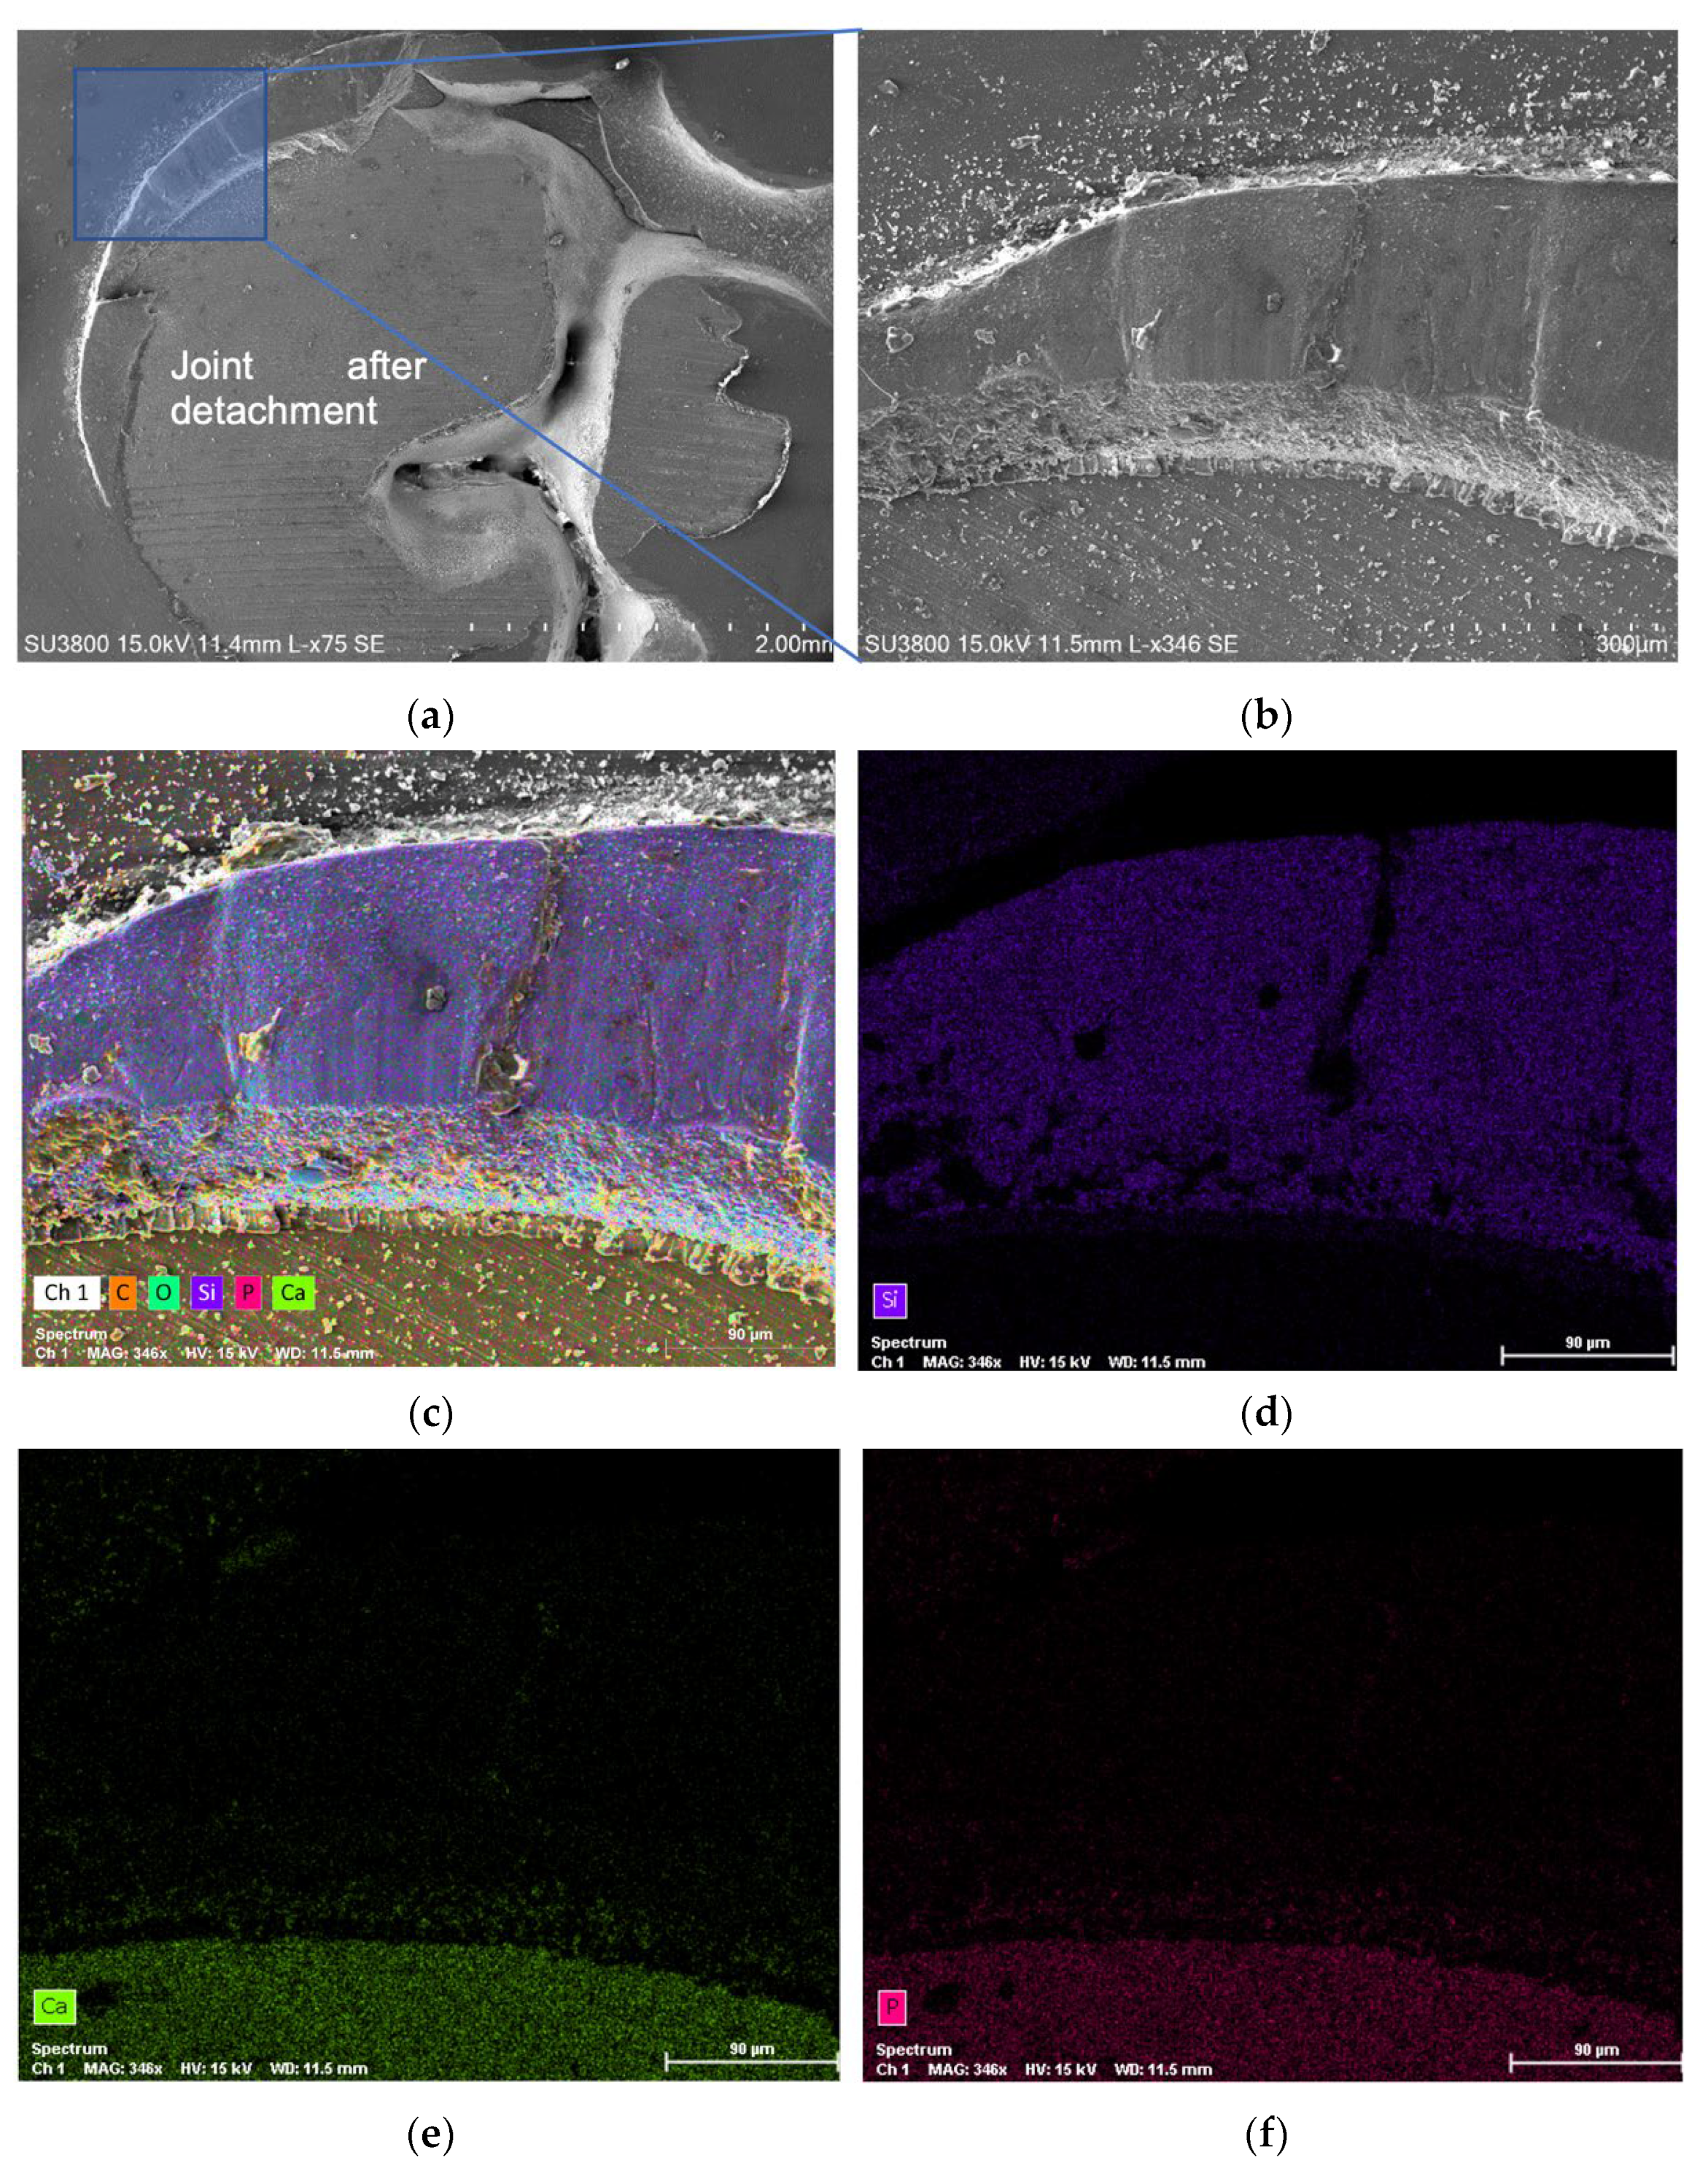

3. Results